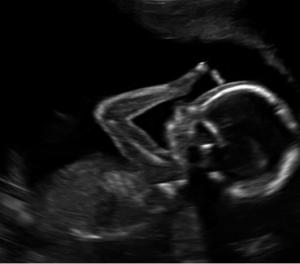

Pais de 4 filhos a quem procuram educar esmeradamente na fé católica, eles compartilharam recentemente uma ultrassonografia da sua quinta criança, uma menina que está a caminho.

A imagem mostra uma cena tocante e surpreendente. O casal a descreve:

“Interrompemos nosso ‘feed’ de santos para compartilhar esta bela imagem da vida. Nossa doce menina, com 19 semanas no útero, já está fazendo o sinal da cruz! A vida é tão preciosa!”